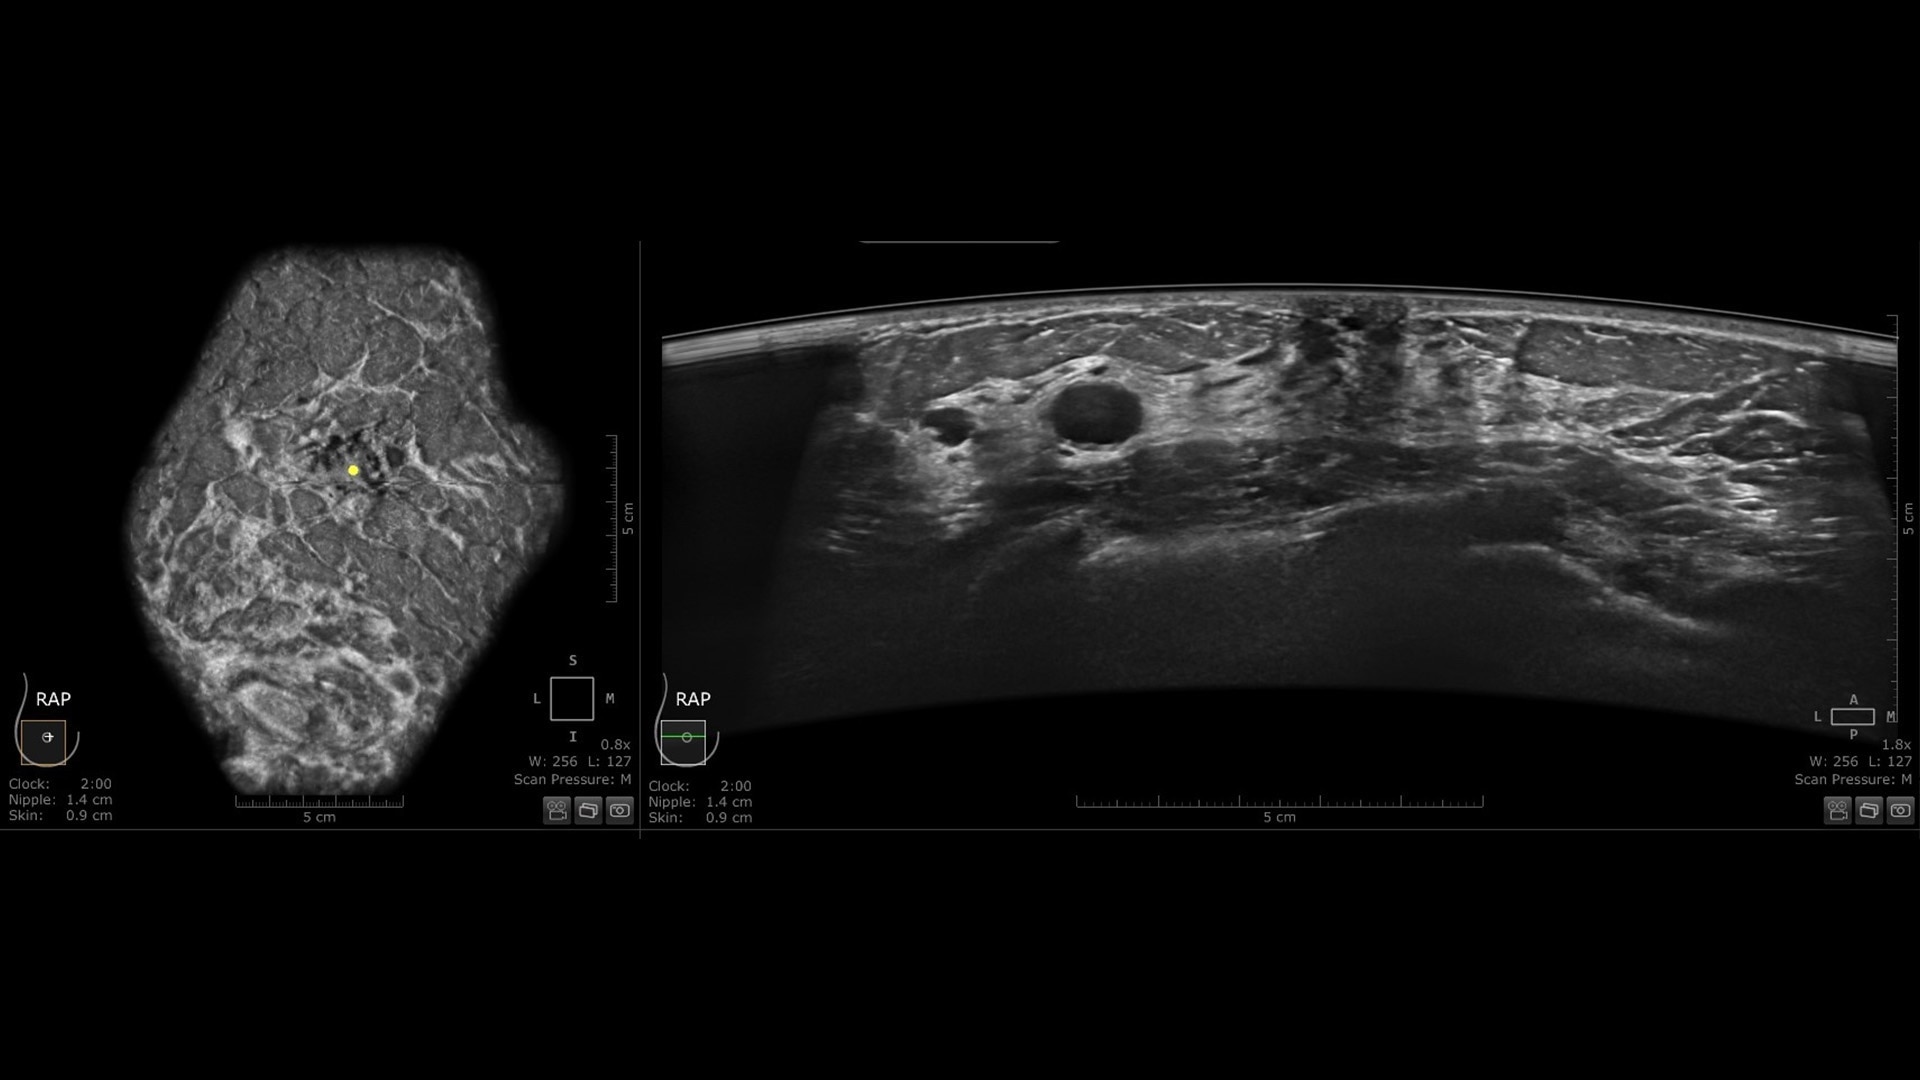

Productivity powered by AI

Boost clinical confidence and efficiency with AI-driven scanning and reading